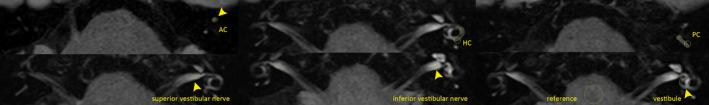

Four-hour-delayed 3D-FLAIR MRIs in patients with acute unilateral peripheral vestibulopathy.

Overall, the inter-rater agreement for gadolinium enhancement was 0.886 (Cohen's kappa coefficient). Enhancement was observed in 26 patients (49%), most frequently in the vestibule (n = 20), followed by the anterior (n = 12), horizontal (HC, n = 8), posterior canal (n = 5), and superior (n = 3) and inferior (n = 1) vestibular nerves. In multivariable logistic regression analysis, the enhancement was associated with decreased HC gain in video head-impulse tests (p = 0.036), increased interaural difference in ocular vestibular-evoked myogenic potentials (p = 0.001), and a longer onset-to-MRI time span (p = 0.024). The sensitivity and specificity were 92.3% and 81.5%, respectively, with an area under the curve of 0.90 for predicting gadolinium enhancement.

Robust gadolinium enhancement was observed on 4-hour-delayed 3D-FLAIR images in nearly half of the patients with AUPV/VN, with a good correlation with the results of neurotologic evaluation. The positivity may be determined by the extent of vestibular deficit, timing of imaging acquisition, and possibly by the underlying etiology causing AUPV/VN. MRIs may aid in delineating the involved structures in AUPV/VN.